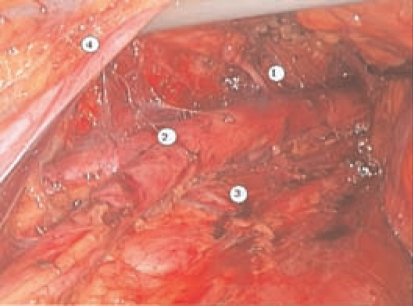

The next step is to reach the right common iliac vessels. The peritoneal sac is elevated from the left common iliac vein and then from the sacral promontory. The bifurcation of the inferior vena cava is then identified. The right common iliac vein and the right common iliac artery are freed using blunt dissection. The right common iliac artery is followed in a caudal direction down to the level of its bifurcation. The right ureter is then elevated and separated from the iliac vessels and the psoas muscle. At this time, the right lateral common iliac nodes and the presacral nodes are removed. The precaval nodes are identified and detached from the inferior vena cava. Once these steps have been accomplished, the nodal dissection is considered complete (Figure 3).

Figure 3.

Laparoscopic extraperitoneal paraaortic lymphadenectomy: (1) Inferior mesenteric artery; (2) aortic bifurcation; (3) lumbar artery and vein; (4) left ureter.